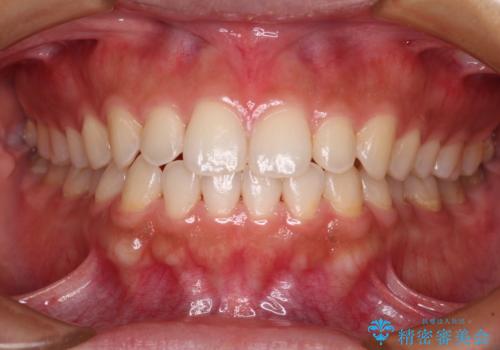

前歯が折れたついでに歯並びも改善 矯正治療と前歯のセラミック治療